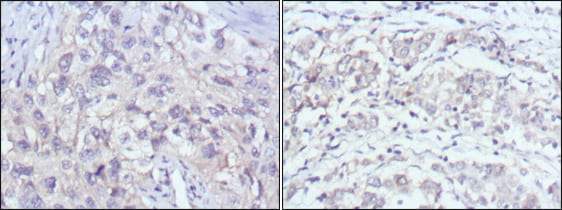

分类: 科研抗体货号: 20345别名: Isl-1; ISLET1应用: IHC,IF反应种属: Human,Mouse,Rat,Rabbit

分类: 科研抗体货号: 20344别名: Isl-1; ISLET1应用: IHC,IF反应种属: Human,Mouse,Rat,Rabbit